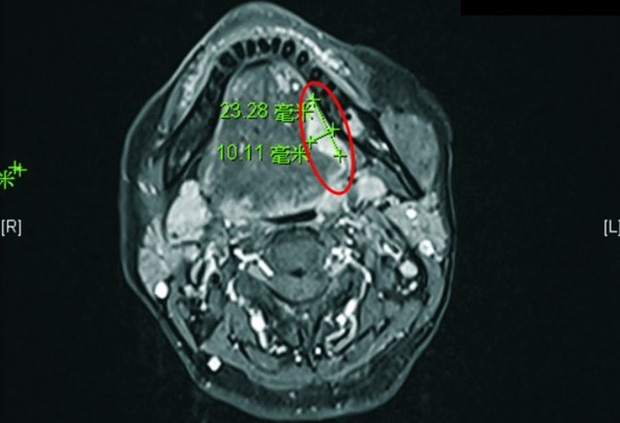

Khoanh đỏ: Hình ảnh X-quang của khối u

Sau khi thăm khám, bác sĩ phát hiện vết loét ở lưỡi đã tiến triển thành ung thư lưỡi, cần bố trí mổ ngay. Bác sĩ Chen chỉ ra rằng vì ung thư lưỡi có thể di căn đến các hạch bạch huyết ở cổ hoặc thậm chí các cơ quan khác, nên cần phải thu xếp tất cả các cuộc kiểm tra trong vòng một tuần và loại bỏ khối u càng sớm càng tốt. May mắn thay, ca mổ diễn ra suôn sẻ, cô đã kịp bình phục và xuất viện sau 5 ngày.